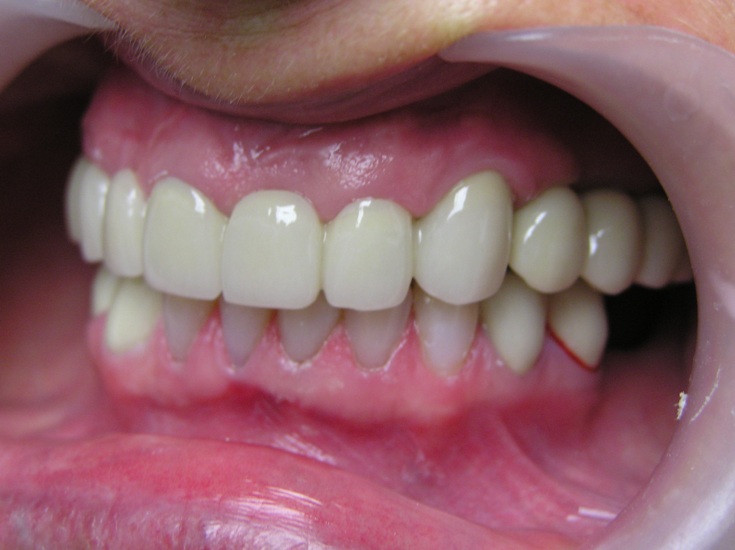

Result: Complete and total restoration of maxillary dentition aesthetics.

At present the patient’s mandible is being rehabilitated.